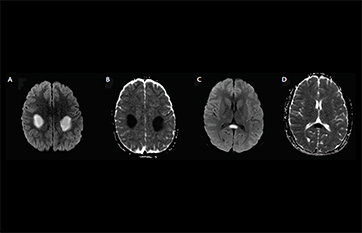

Charcot marie tooth disease radiology. X-linked Charcot-Marie-Tooth disease CMT1X is the second most common form of inherited neuropathy. Gallardo E Garcia A Combarros O Berciano J. MRI is an ideal method for identifying areas of muscle atrophy and fatty infiltration.

Spectrum of clinical and magnetic resonance imaging features in. Charcot-Marie-Tooth disease type 1A duplication.

Mri Findings In X Linked Charcot Marie Tooth Disease Associated With A Novel Connexin 32 Mutation Clinical Radiology

Corticospinal Tract Mri Hyperintensity In X Linked Charcot Marie Tooth Disease Journal Of Clinical Neuroscience